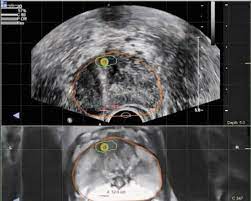

Memorial Sloan Kettering

Memorial Sloan Kettering from